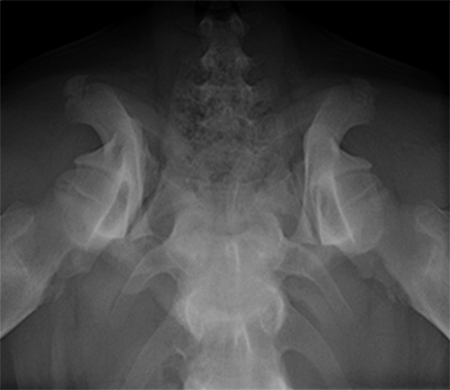

A 5-month-old spayed female labrador retriever puppy weighing 22.0 kg presented with bilateral hind limb weakness and a bunny-hopping gait in the hind limbs. Physical examination revealed bilateral hip instability (positive Ortolani sign) and mild pain on full extension of the hips. Slight crepitus was palpated in the left hip. The gluteal muscles appeared to have mild atrophy. The neurological exam was normal. Radiographic examinations revealed bilateral hip subluxation and a distraction index of 0.5 of the right hip and 0.7 of the left hip (Fig 3). No evidence of osteoarthritis was observed.